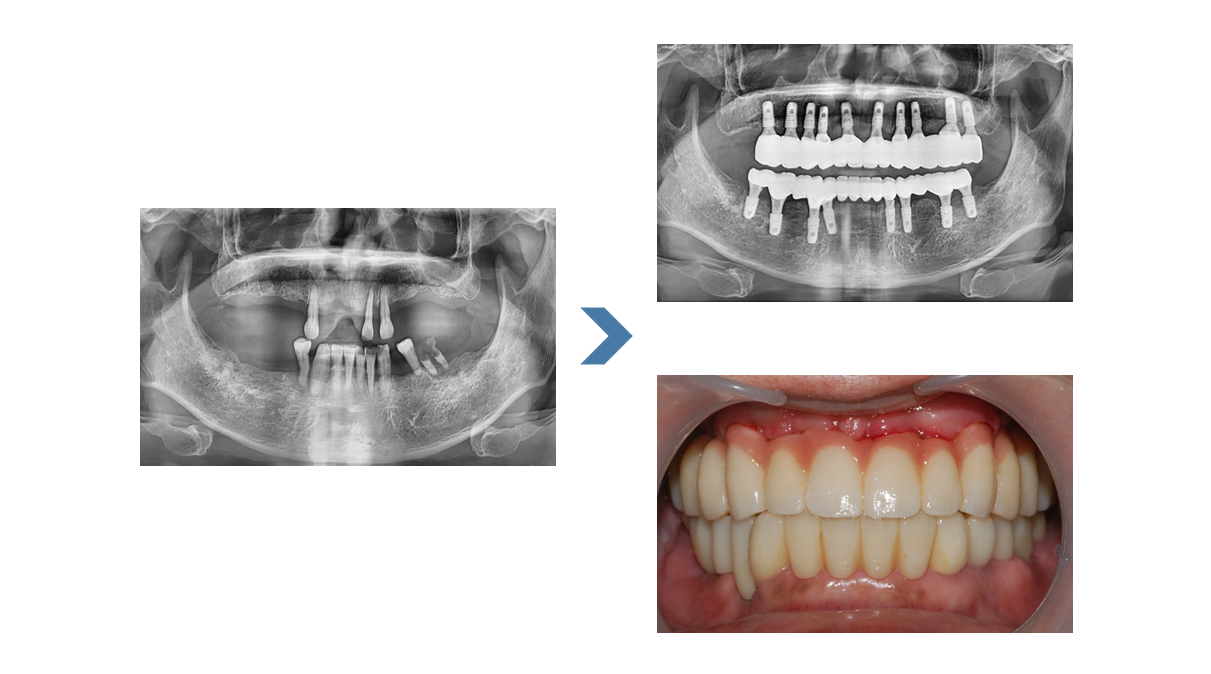

치주질환이 심해졌거나 나이가 들면서 잇몸상태가 안 좋아져 치아를 받치고 있는 치조골이 많이 소실되면 치아가 흔들립니다.

이때 치아가 얼마 남아있지 않아 틀니와 임플란트를 고려하게 되는데 틀니는 잇몸 위에 얹는 방식이라 씹을 때 잇몸에 압박이 가해지고

제대로 힘들 받기 어려운 점이 있다면 임플란트는 식립을 하여 사용하기 때문에 자연치아만큼 편안한 사용이 가능합니다.

전체 임플란트의 대상자는 주로 고령자입니다.

때문에 전신상태인 건강, 당뇨 등 수술에 영향을 주는 질환 유무를 파악하고

전문의와 상담을 통해 진행 유무를 확인하시는 것이 중요합니다.